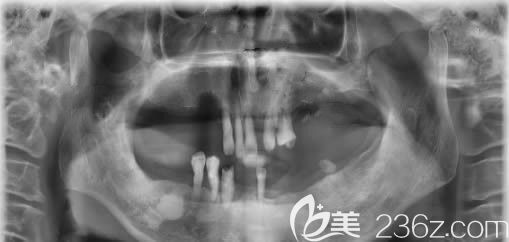

種牙前的CT片,牙齒掉的只剩9顆松動牙,讓我吃飯成為了一種折磨:↑↑